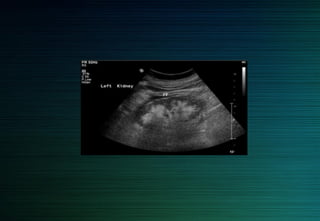

Mesure de la taille du rein

Variabilité inter/ intra observateurs

Erreurs par défaut

Plus grande dimension longitudinale

axe bivalve oblique en bas et dehors

 répéter 3 fois la même mesure si < 11cm